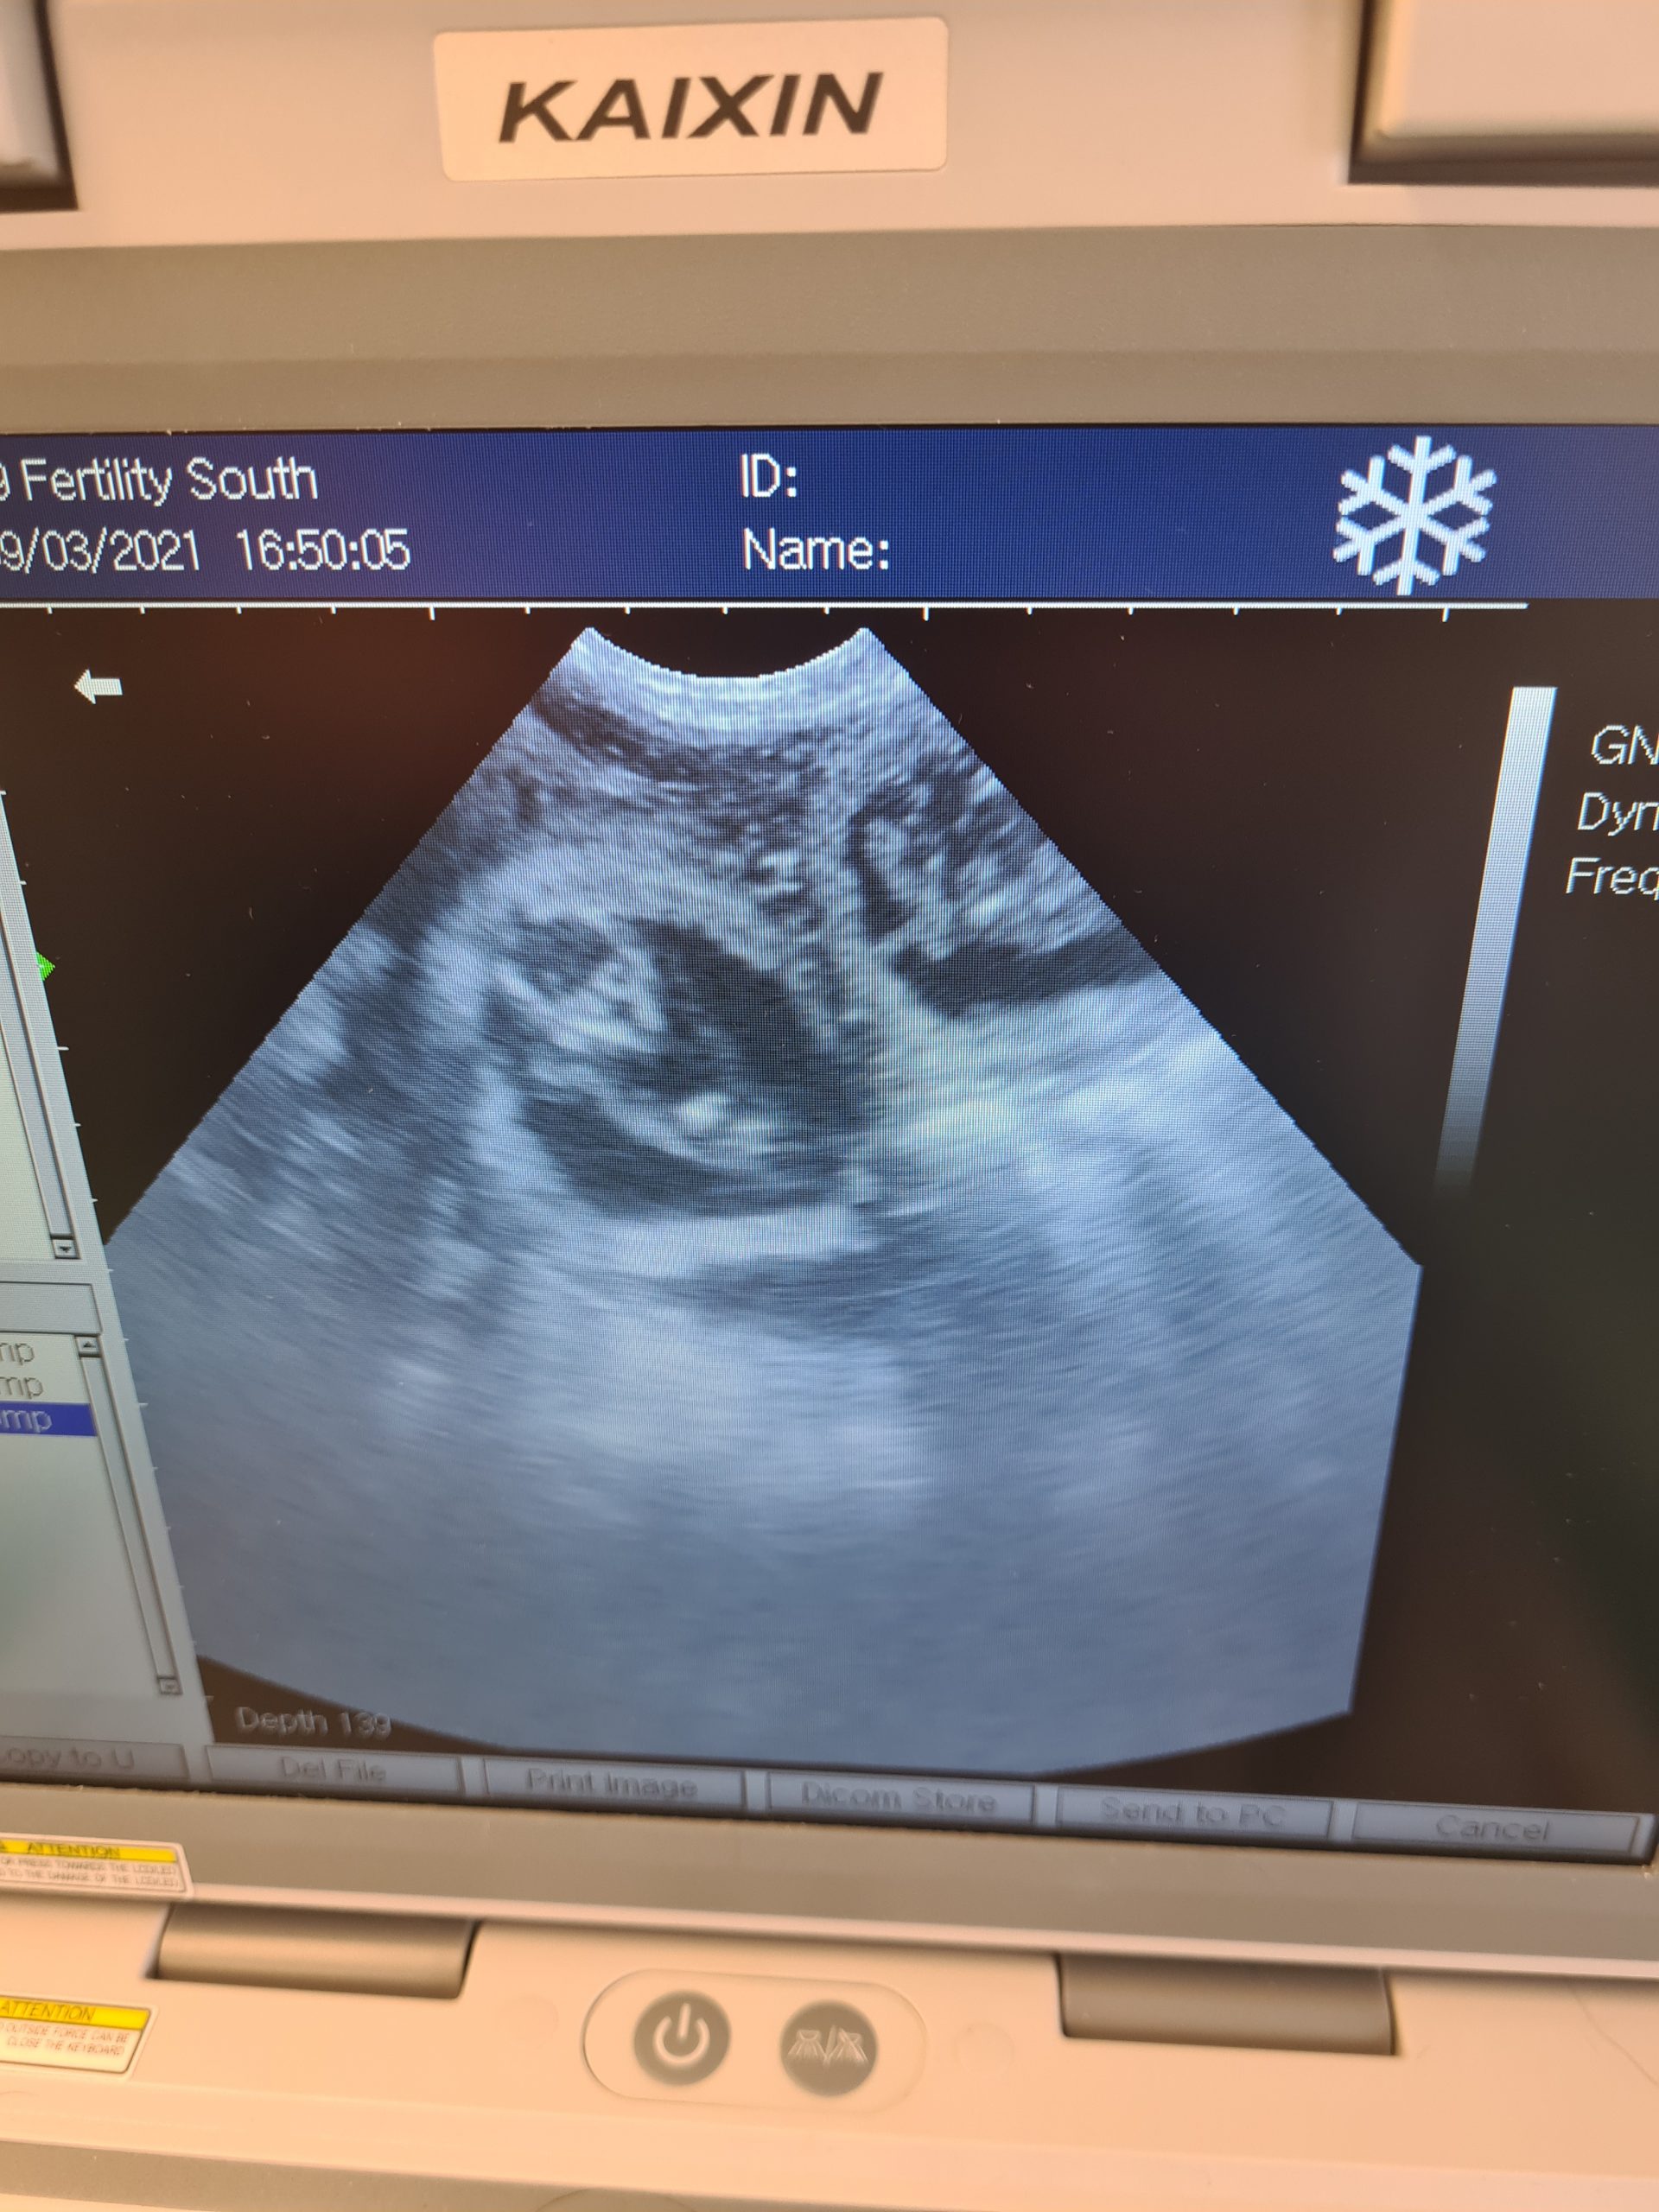

Daschund and Maltese scans following cytology and a.i. here at the clinic

Day 32 5 pups seen